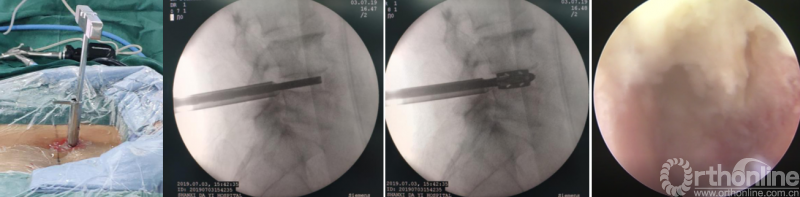

第一步“定”:X线定位在上位椎体下关节突下三分之一部;

第十步“置”:置入融合器、经皮钉。

具体操作视频:http://res.orthonline.com.cn/video/5/belif.mp4

病例分享:(滑动查看)